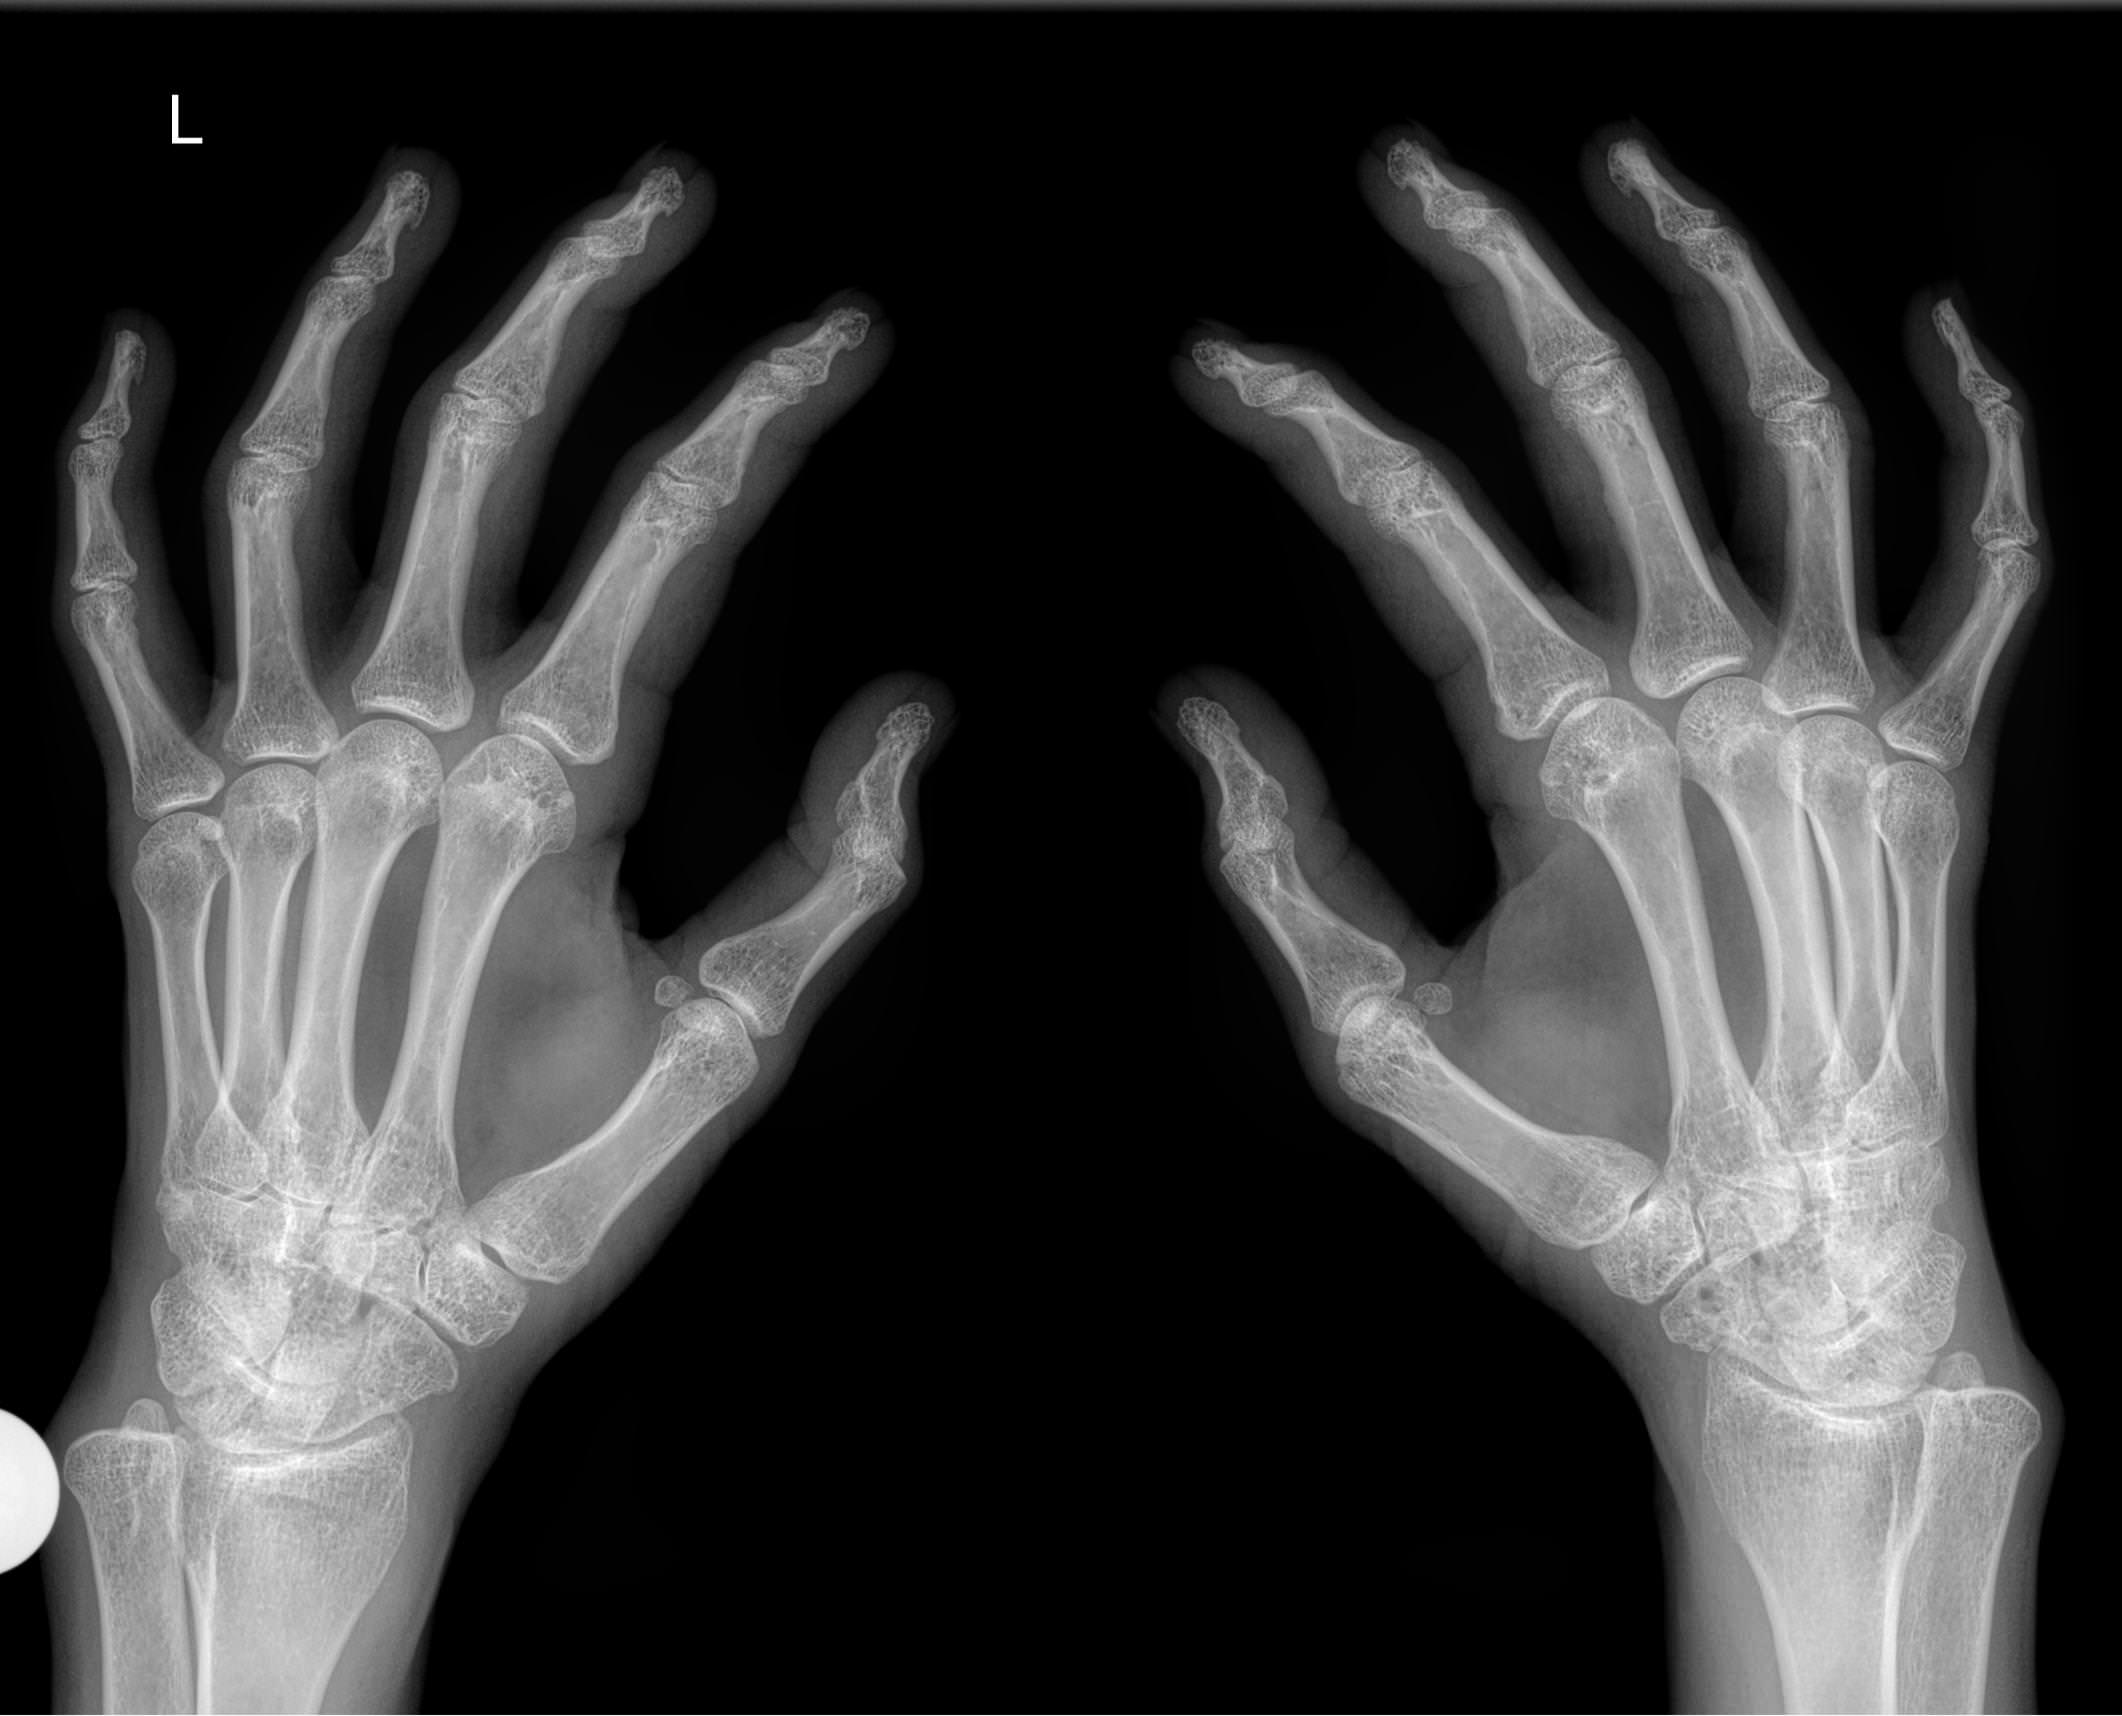

Рентген костей и суставов ― стандартная диагностическая процедура. Она основана на проникающей способности рентгеновского излучения, которое по разному задерживается в тканях разной плотности. Соответственно, изображение тканей на снимке будет в виде пятен также разных оттенков серого, от белого до практически черного. Как наиболее плотные, кости визуализируются как самые яркие. Современная аппаратура испускает минимальное излучение, составляющее минимальную часть от предельно допустимой годовой дозы.

Хронические системные патологии обычно поражают дистальные отделы верхних конечностей одновременно. Именно для этого и требуется снимок обеих кистей. В случае травмы или выявления врожденной аномалии рентгенограмма двух рук необходима для сравнения анатомических особенностей.

При изучении снимка рентгенолог обращает внимание на все образования, расположенные в области кистей, но в протокол преимущественно вносит только обнаруженные патологические изменения:

• В суставных щелях;

• В соответствии суставных поверхностей друг другу;

• В структуре костной ткани и надкостницы;

• В мягких тканях.

Если будут обнаружены любые новообразования, указывает их размер и локализацию.